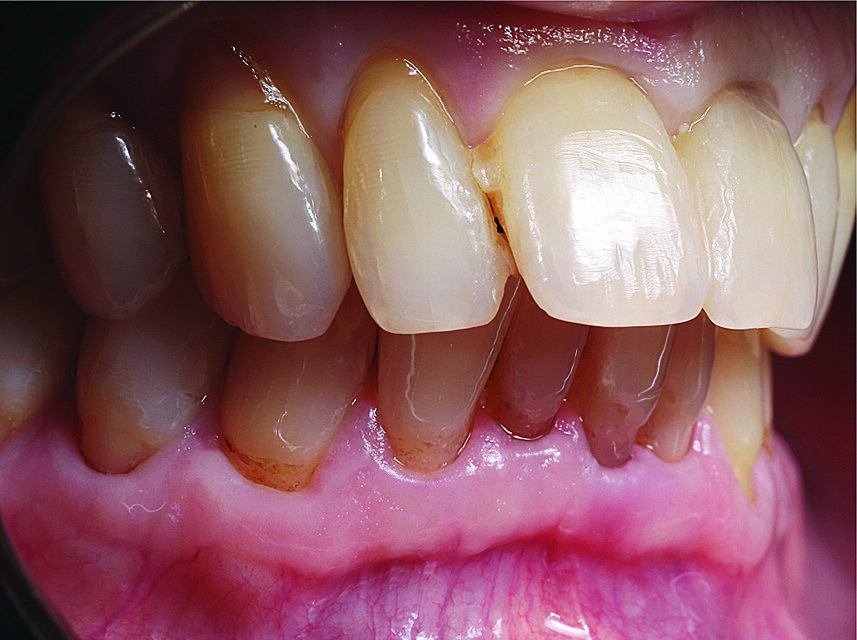

Budući da se to nije moglo isključiti za zub 21, u narednim posjetima provedeno je endodontsko liječenje s naknadnim punjenjem korijenskog kanala s MTA-om do pukotine (Slika 3.). Budući da je pacijent izrazio želju da se ne narušava estetika, za splintiranje je upotrijebljena palatinalna udlaga od PMMA-e (Slika 4.). Nakon tri mjeseca uočena je sve veća promjena boje zuba 21 i perzistentna pomičnost II. stupnja (Slika 5.). Nakon detaljnog informiranja o raznim mogućnostima liječenja kliničar i pacijent donijeli su odluku o implantoprotetskoj terapiji. CBCT snimljen tijekom planiranja terapije (Slika 6.), pokazao je blizak odnos prema vestibularnoj koštanoj lameli (položaj korijena I. razreda)14. Da bi se stvorio stabilan profil mekog i tvrdog tkiva i pacijentu što prije osigurao dobar estetski rezultat, kliničar se odlučio na imedijatnu implantaciju uz primjenu socket shield tehnike.

Slika 5. Stanje nakon tri mjeseca: promjena boje na zubu 21 cervikalno

Slika 6. CBCT prije implantacije: vrlo tanka bukalna koštana lamela i bliski odnos korijena s korteksom